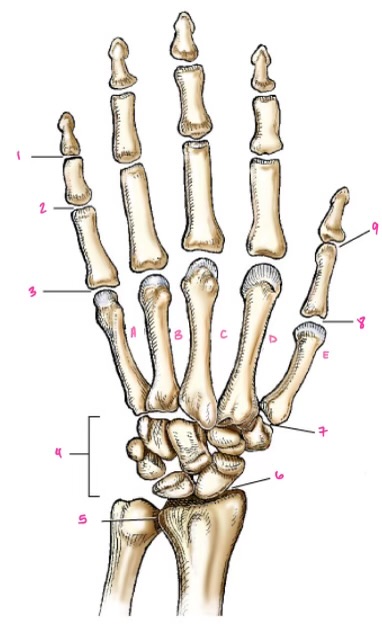

1

1

Hamate

2

2

Capitate

3

3

pisiform

4

9

Trapezoid

5

10

Trapezium

6

11

Scaphoid

7

14

Lunate

8

15

Triquetrum

9

16

Pisiform

10

17

Capitate

11

18

Hamate

1

Distal interphalangeal

13

2

Proximal Interphalangeal

14

3

Metacarpophalangeal

15

4

Intercapals

16

5

Distal radioulnar

17

6

Radiocarpal

18

7

Carpometacarpals

19

8

Metacarpophalangeal

20

9

Interphalangeal

7

Trapezoid

22

8

Trapzium

23

9

Capitate

24

10

Scaphoid

25

11

Lunate

26

13

Carpus

27

14

Triquetrul

28

15

Hamate

29

16

Metacarpus

30

17

Phalanxes